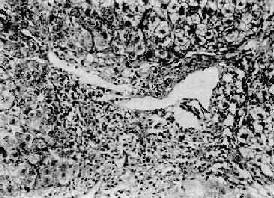

本型病变可见肝细胞坏死严重而广泛。肝索解离,肝细胞溶解,出现弥漫性的大片坏死。坏死多自小叶中央开始,向四周扩延,仅小叶周边部残留少数变性的肝细胞。肝窦明显扩张充血并出血,Kupffer细胞增生肥大,并吞噬细胞碎屑及色素。小叶内及汇管区有淋巴细胞和巨噬细胞为主的炎性细胞浸润(图10-40)。残留的肝细胞再生现象不明显。肉眼观,肝体积显著缩小,尤以左叶为甚,重量减至600~800g,质地柔软,表面被膜皱缩(图10-41)。切面呈黄色或红褐色,有的区域呈红黄相间的斑纹状,故又称急性黄色肝萎缩或急性红色肝萎缩。

急性重型肝炎

图10-40 急性重型肝炎

肝细胞大片坏死消失,小叶中心部最重,周边部残存的肝细胞变性。坏死区有炎性细胞浸润